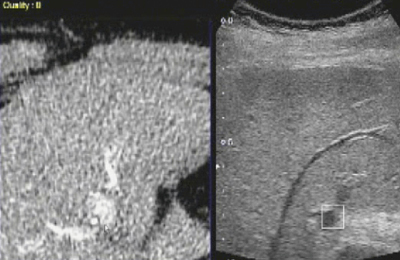

焼灼開始から約15分で治療が終了するが,追加穿刺が必要かどうかをSmart Fusionの画像により,CTデータも参考にしながら評価を行う(図5)。

治療直後に,再びSmart Fusion下のソナゾイド造影を行い,腫瘍近くの比較的太い血管が閉塞せずに残っていることが認められた。血流が増加した領域が辺縁部にリング状に見られるが,これは炎症反応を見ていると考えられる。また,この症例では十分マージンも取れていることが評価できた(図6)。

![]() 図5 治療から15分後の焼灼モニタ 焼灼範囲と腫瘍の位置関係がよくわかる(b)。 |

![]() 図6 RFA治療直後のソナゾイド造影超音波画像(b) 治療前の焼灼予定範囲(aおよびbの緑の円)と 治療後の実際の治療域の関係がよくわかる(b)。 |